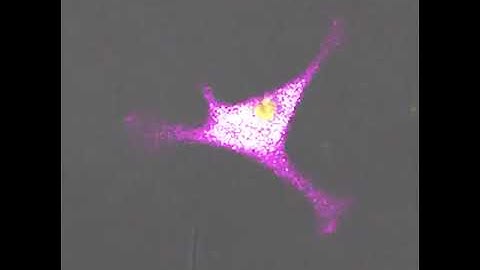

Cluster of IFN-gamma-producing T cells